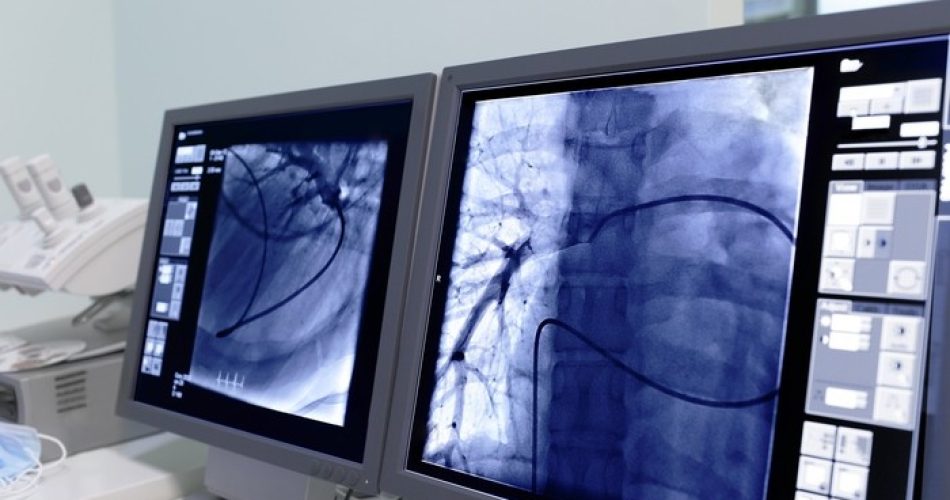

Monitor screen in radiology. (foto Ansa)